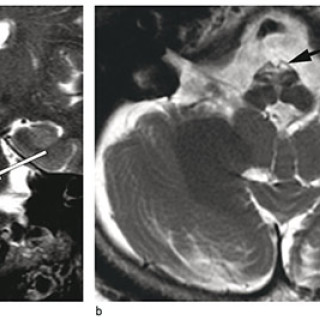

En kvinne fikk forverring av en hodepine som hadde debutert flere måneder i forveien. Hun utviklet deretter uvanlige kognitive symptomer og ble innlagt i sykehus. Pasienten, som var i 40-årene, hadde fra tidligere astma og var slankeoperert med gastrisk bypass. Det siste halvåret før innleggelsen hadde hun vært sykmeldt grunnet en oksipital, bilateral hodepine som oppsto under en arbeidskonflikt, men vedvarte trass i omplassering i ny stilling. Hodepinen hadde et fluktuerende forløp, med hodepinefrie dager. Den siste måneden var imidlertid hodepinen blitt konstant, og kvinnen hadde tatt...